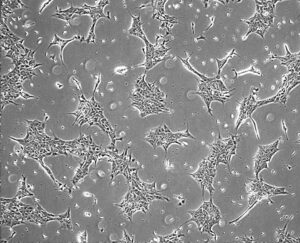

Nuestra línea de investigación busca comprender los mecanismos por los cuales Aβ induce neurodegeneración, con especial foco en el rol de APP como receptor y en la participación de la proteína G heterotrimérica Go como vía de señalización patológica. Para ello, utilizamos enfoques que combinan técnicas avanzadas de microscopía, biología celular, molecular y bioquímica, junto con modelos neuronales humanos derivados de células madre pluripotentes inducidas.